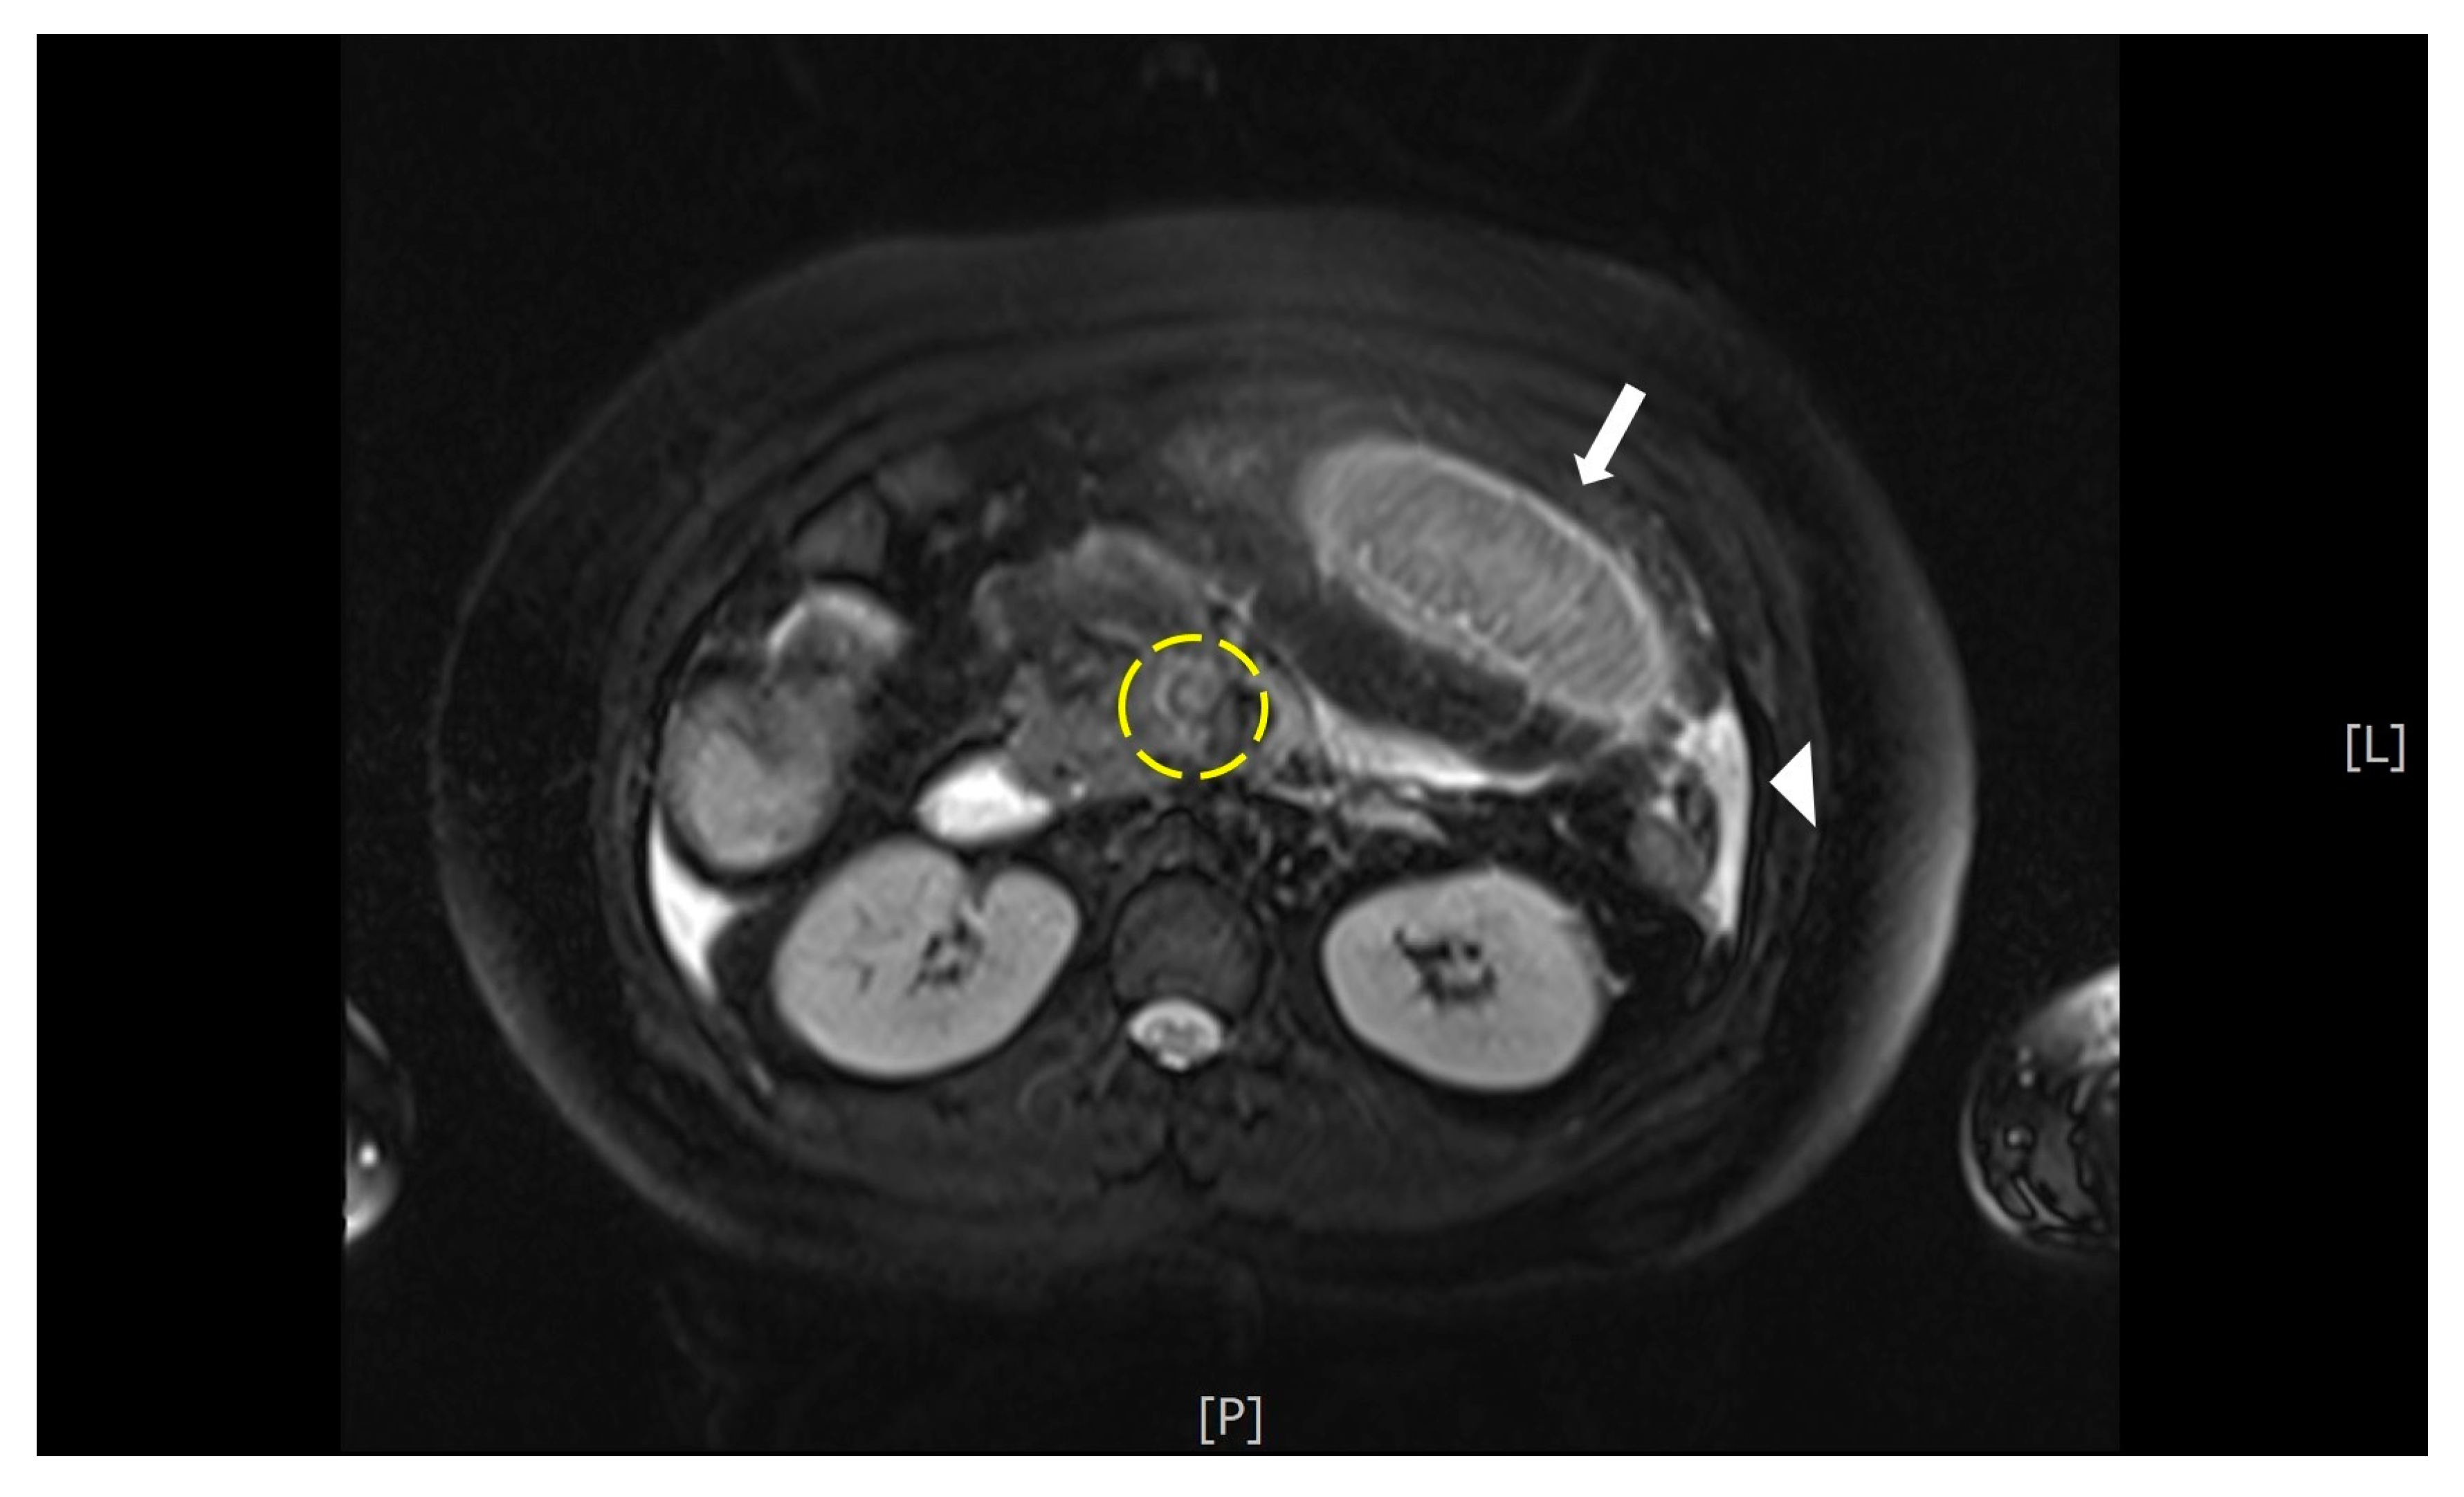

Abdominal ultrasonography revealed a living 10-week-old fetus, mild maternal ascites, and no sonographic evidence of acute cholecystitis or appendicitis. Magnetic resonance imaging (MRI) was performed and demonstrated a T2 hyperintense filling defect within the superior mesenteric vein (SMV), small bowel wall thickening, and ascites (Figure 1). With a suspected diagnosis of bowel ischemia secondary to SMV thrombosis, contrast-enhanced abdominal and pelvic CT (BrightSpeed, General Electric Medical System, Milwaukee, WI, USA), with 5 mm slice thickness, following administration of intravenous contrast was subsequently performed. The CT images demonstrated a filling defect within the main portal vein that extended inferiorly into the SMV and its branches as well as venous engorgement of the SMV branches (Figure 2). Additional findings included circumferential small bowel wall thickening and hypoenhancement as well as edematous changes within the adjacent mesenteric fat.

Figure 1. MRI This T2- fat saturation image demonstrates a hyperintense filling defect within the superior mesenteric vein (yellow circle). There is also thickening of the wall of a small bowel loop (arrow), and a small amount of ascites (arrow head).